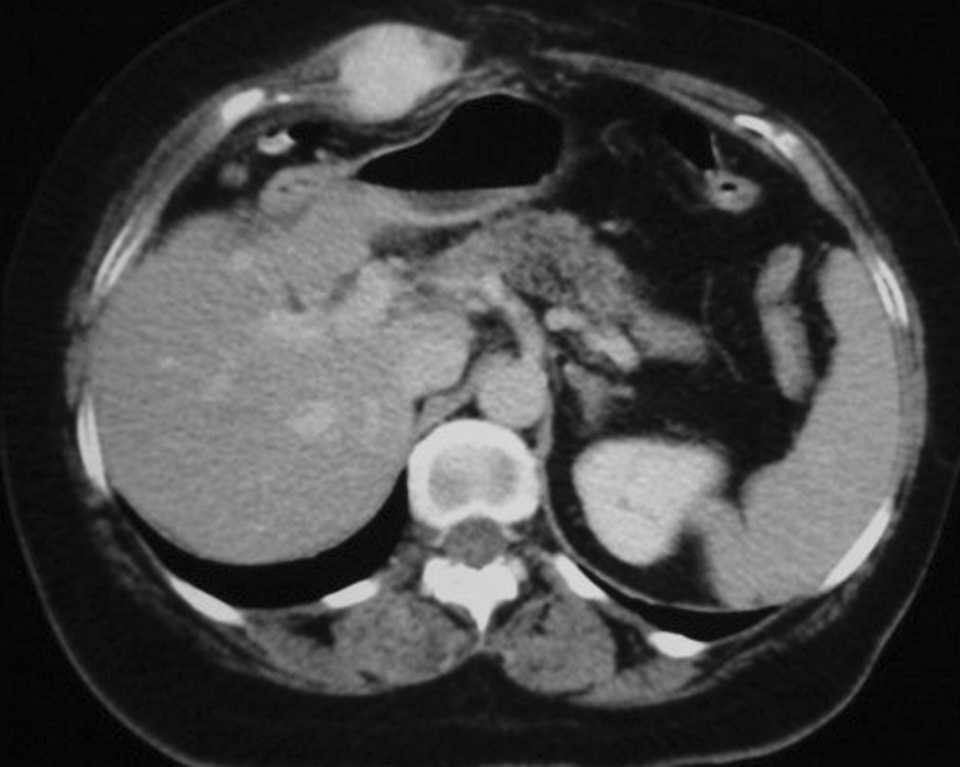

En agosto de 2003, la paciente acudió por molestias en la laparotomía. En la exploración se observaba una tumoración dura y dolorosa a la palpación. Se realizó una TC (fig. 1) en la que se observó un tumor extraperitoneal compatible con recidiva. Se practicó una pun-ción-aspiración con aguja fina, que reveló una metástasis de adenocarcinoma. La TEP mostró una área hipermetabólica en el epigastrio compatible con una recidiva única en la pared abdominal (fig. 2). Se realizó la exéresis de la lesión (fig. 3) y la colocación preperitoneal de malla de polipropileno. El estudio histológico reveló una metástasis de adenocarcinoma con márgenes libres de tumor.